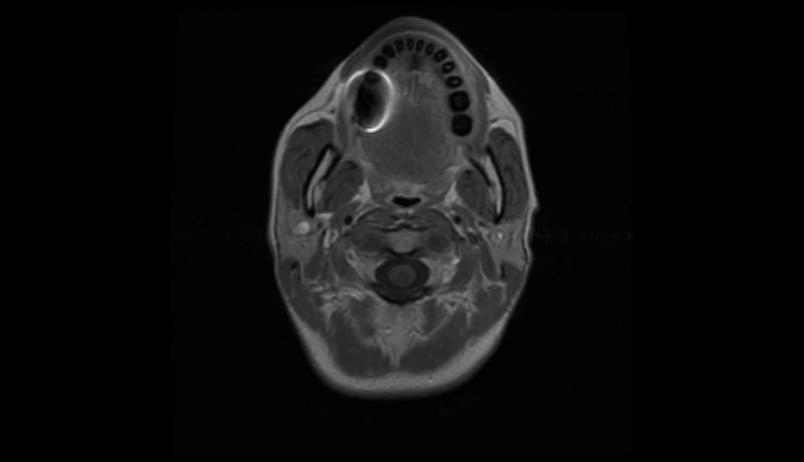

MRI of the cervical and thoracic spine showed a diffuse, intramedullary abnormal signal extending from the medulla down to approximately the mid-thoracic level. There was swelling in portions of the spinal cord, particularly in the lower cervical cord where there was contrast enhancement (Figure 1 [Fig. 1], Figure 2 [Fig. 2], Attachment 1 [Att. 1]). The MRI of the brain was normal.